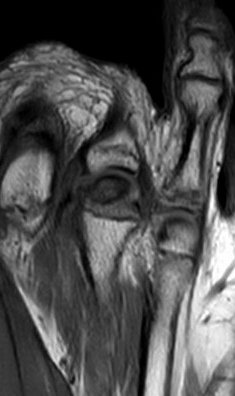

MRI